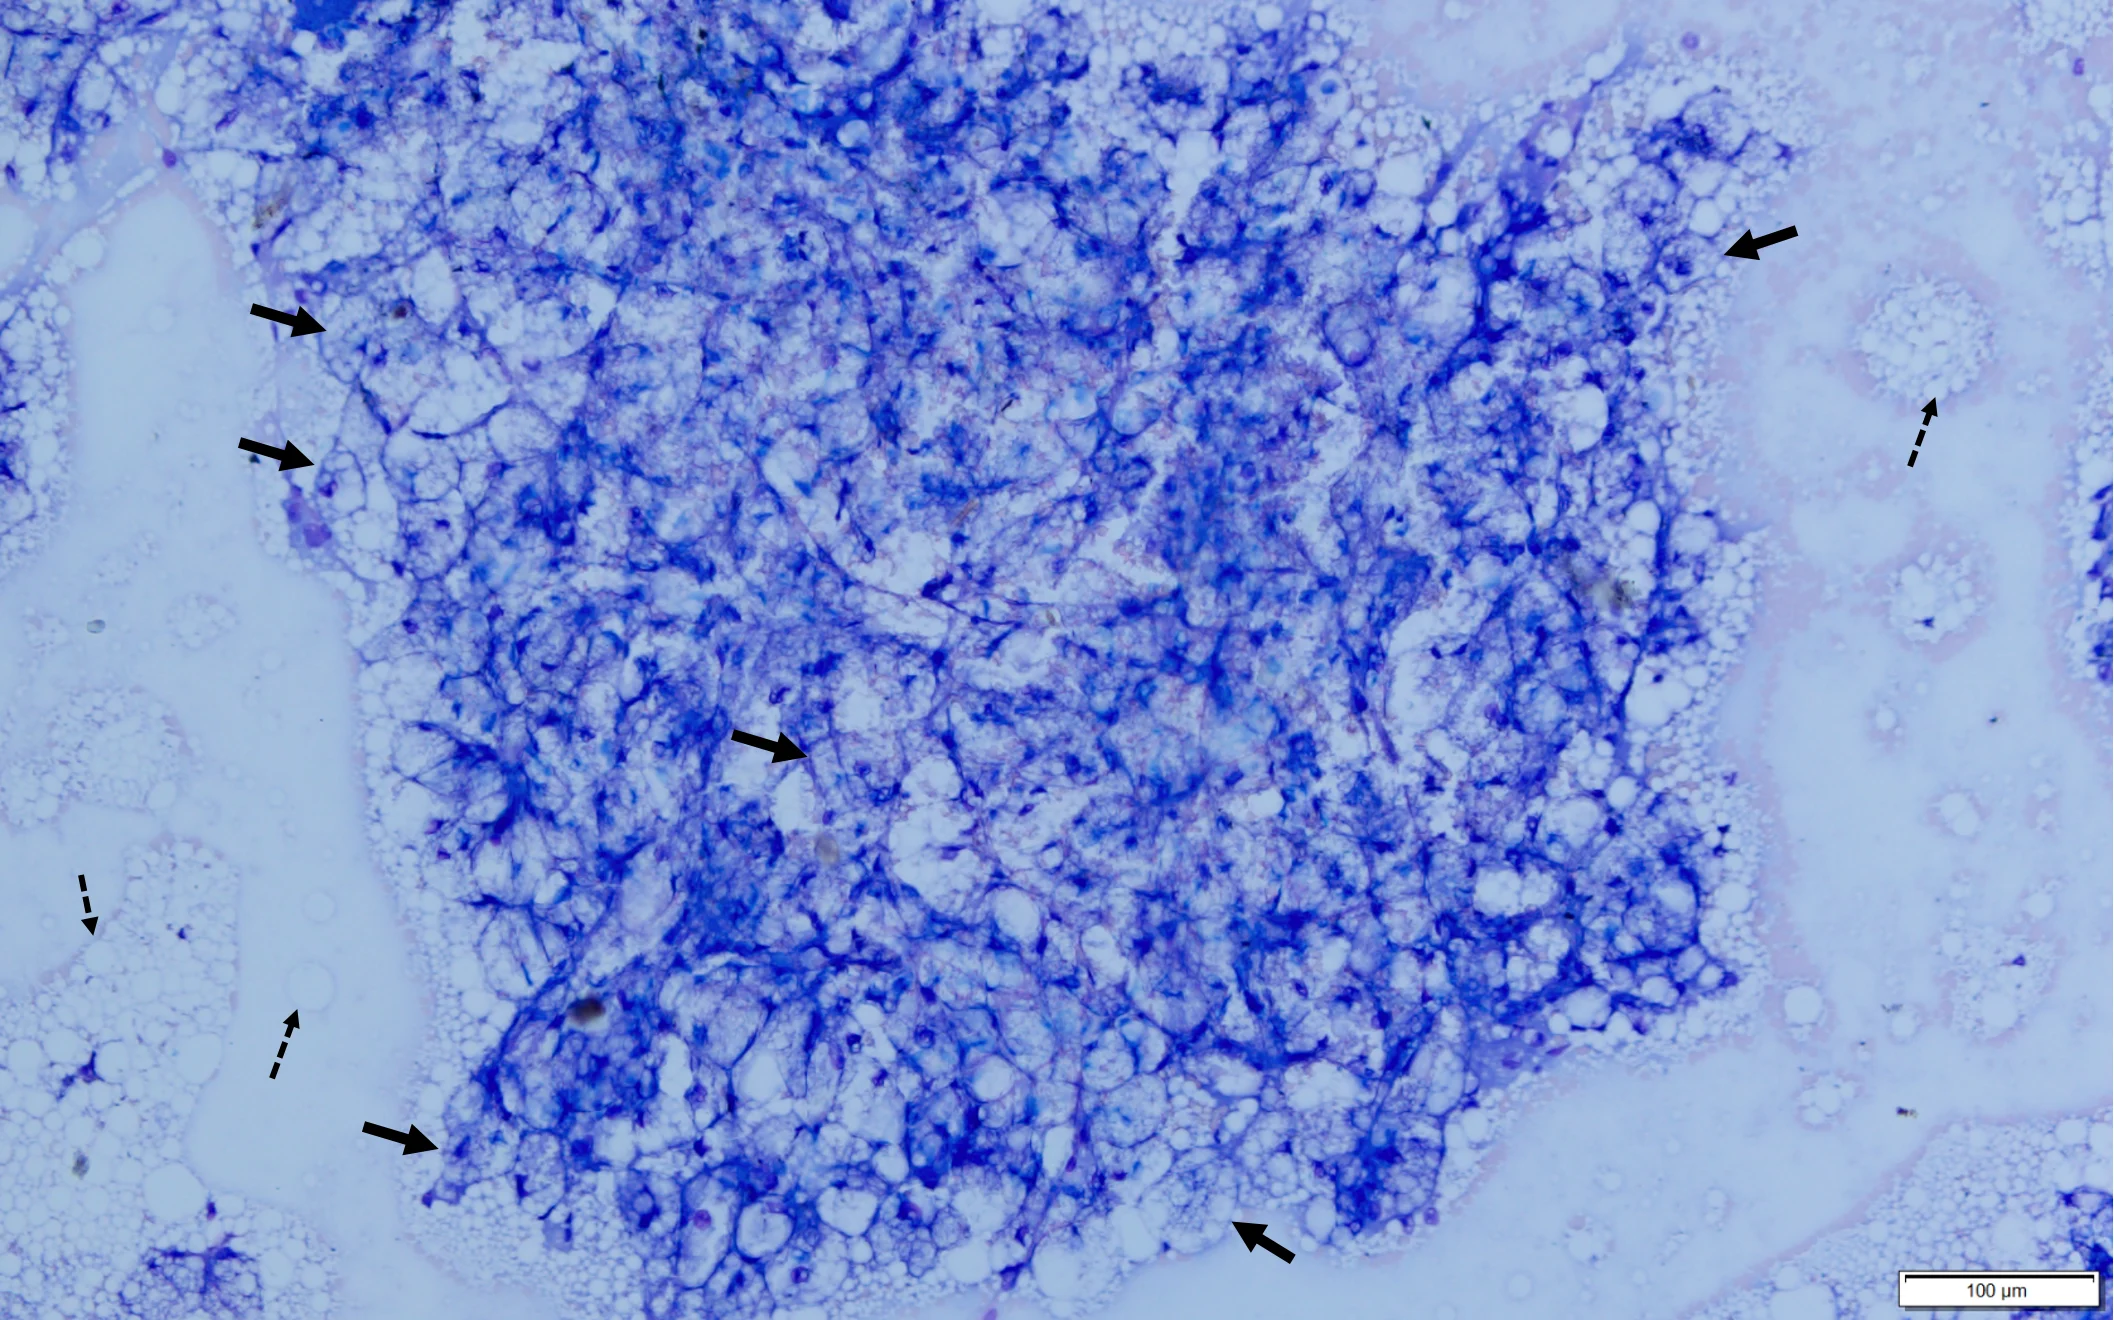

Abdominal ultrasonography revealed an enlarged liver with rounding of the caudal ventral margin. The hepatic parenchyma was hyperechoic and hyperattenuating, suggestive of lipid deposition. A fine-needle aspirate of the liver revealed abundant hepatocytes with marked vacuolation consistent with lipid (Figures 1 and 2).

Fine-needle aspirate from the liver of a cat. A cohesive sheet of hepatocytes (solid arrows) can be seen. Cytoplasm of hepatocytes is markedly distended with large (ie, macrovesicular) and small (ie, microvesicular) clear vacuoles that make observation of hepatocytes difficult. Darkly pigmented material (bile casts; circles) can be seen between cells, indicating cholestasis. Numerous free lipid droplets (dashed arrow) are also present in the background, but although this finding is typical with hepatic lipidosis, it is not diagnostic, as lipid must be within the cells. Modified Wright’s stain, 600× magnification